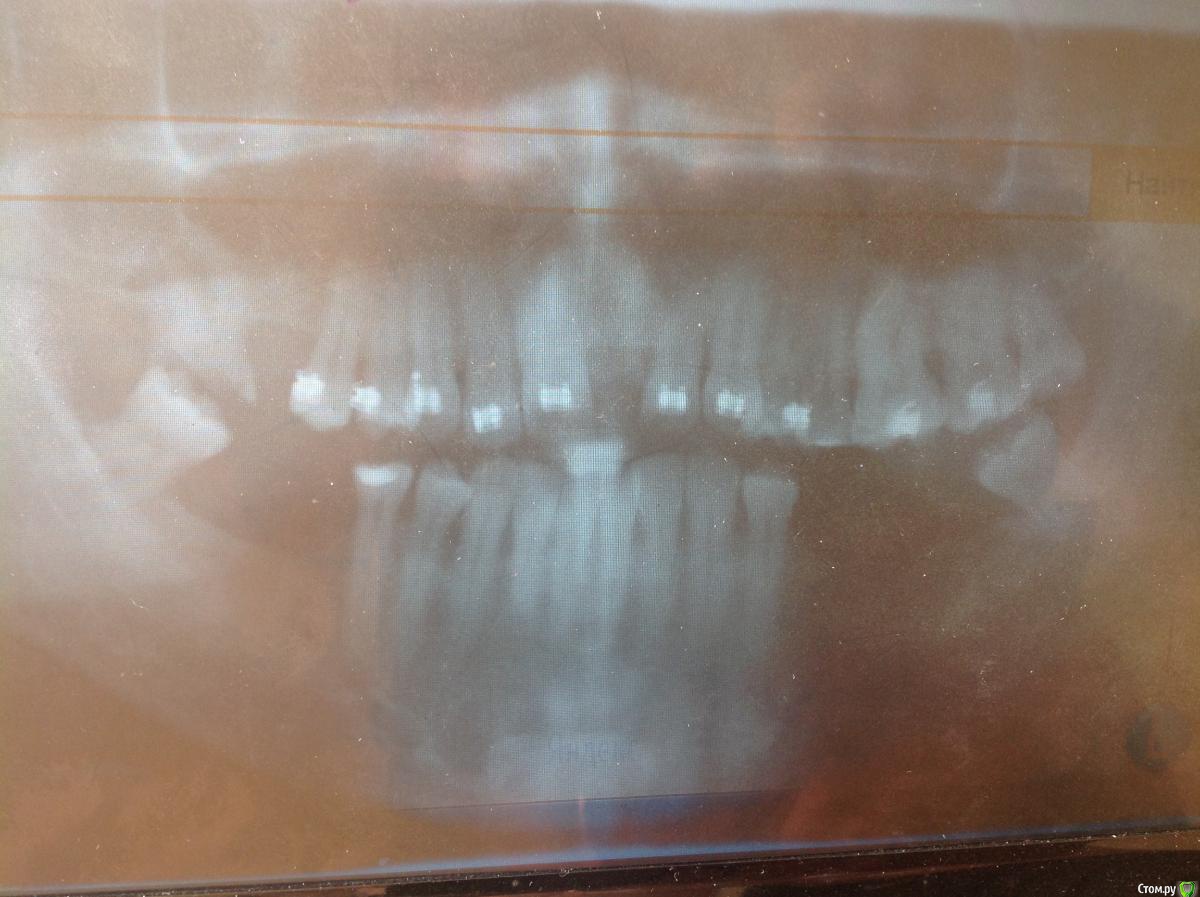

Jeniaspb Опубликовано 20 июля, 2015 Поделиться Опубликовано 20 июля, 2015 Пациент 32 года. Фото к сожалению только те, что есть. По ТРГ верхняя микрогн и нижняя прогнатия, протруз резцов в/ч 132^ и ретрузия резцов н/ч 68^, а так же переднее положение головки н/ч. Идеально сделать гнатич хирургию, но пациент идет в полный отказ, в связи с чем имеются следующие мысли:1) провести ТЭНС терапию с определением положения н/ч, в надежде на то, что она сместится хоть чуточку назад.2) если н/ч сместится каппа на н/ч с последующ окклюз накладками3) б/с на нижн зубн ряд и попыткой смещения дистально премоляров для освобожд места резцам4) б/с на в/ч и попытки камуфляжа этого всего...5) имплантация и затем протезирование.Вопрос самый главный:на сколько велики мои шансы сделать обратное перекрытие, которое я не смогу вернуть?) Ссылка на комментарий